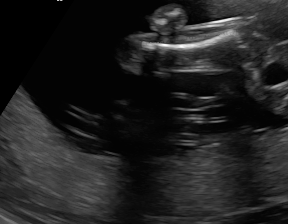

We demonstrate the practical applicability of our method on a challenging medical application, the classification of standardized fetal ultrasound (US) views during prenatal screening. In many countries, US imaging is clinical routine for prenatal health care. The classification of standardized views is important for a consistent, cross-institutional identification of possible abnormalities [47]. Early detection of pathological development can inform following treatment and delivery options [55, 25]. DNNs have shown promising performance to support this task [2]. However, ultrasound images are often hard to interpreted [40]. Anatomical structures have inconsistent appearance [2] and contain different orientations and shapes of anatomical landmarks [1]. Labeled training data is often insufficient as annotating medical images requires significant expertise and is prohibitively expensive in both time and labor. Manifestation of acoustic shadows [17, 44] as shown in Fig. 2(a) as well as different imaging devices as shown in Fig. 2(b) can lead to a domain shift problem for vanilla DNN classifiers. Exploring domain adaptation in fetal US enables DNN classifiers to be effectively utilized on a wider range, which supports identification of abnormalities from varying data sources. This can benefit prenatal healthcare.

We evaluate the proposed method on two fetal US standard plane classification tasks, where the domain shifts are respectively caused by shadow artifacts (Fig. 2(a)) and different image acquisition devices (Fig. 2(b)). For both tasks, images from source and target domains are unpaired and collected independently. We show the key results in the main paper and detailed implementation, network architectures as well as more results in the supplemental Appendix.

The fetal US dataset consists of 2D fetal US images sampled from 2694 2D US examinations with gestational ages between weeks (iFIND Project 555http://www.ifindproject.com/ ). Eight different US systems of identical make and model (GE Voluson E8) were used for the acquisitions to eliminate as many unknown image acquisition parameters as possible. Six different anatomical standard plane locations have been selected by an experienced sonographer, including Four Chamber View (4CH), Abdominal, Femur, Lips, Left Ventricular Outflow Tract (LVOT) and Right Ventricular Outflow Tract (RVOT). The images have additionally been classified by an expert observer as shadow-containing or shadow-free. In this experiment, the source domain contains shadow-free images (see Fig. 2 (b) SF) while the target domain has shadow-containing images from less favorable imaging conditions (see Fig. 2 (b) SC). Training data consists of all six standard planes from the source domain as well as Abdominal, LVOT and RVOT from the target domain. We aim to separate anatomical features (categorical features) and shadow artifacts features (domain features) to obtain generalized anatomical features for achieving high performance of standard plane classification on (4CH, Femur and Lips from target domain). Here, contains 4CH, Abdominal, Femur, Lips, LVOT and RVOT from the source domain and contains Abdominal, LVOT and RVOT from the target domain. Hyper-parameters to in Eq. 11 are for the proposed MIDNet model and is additionally for MIDNet+.

IV-D Experiments on cross-device fetal US